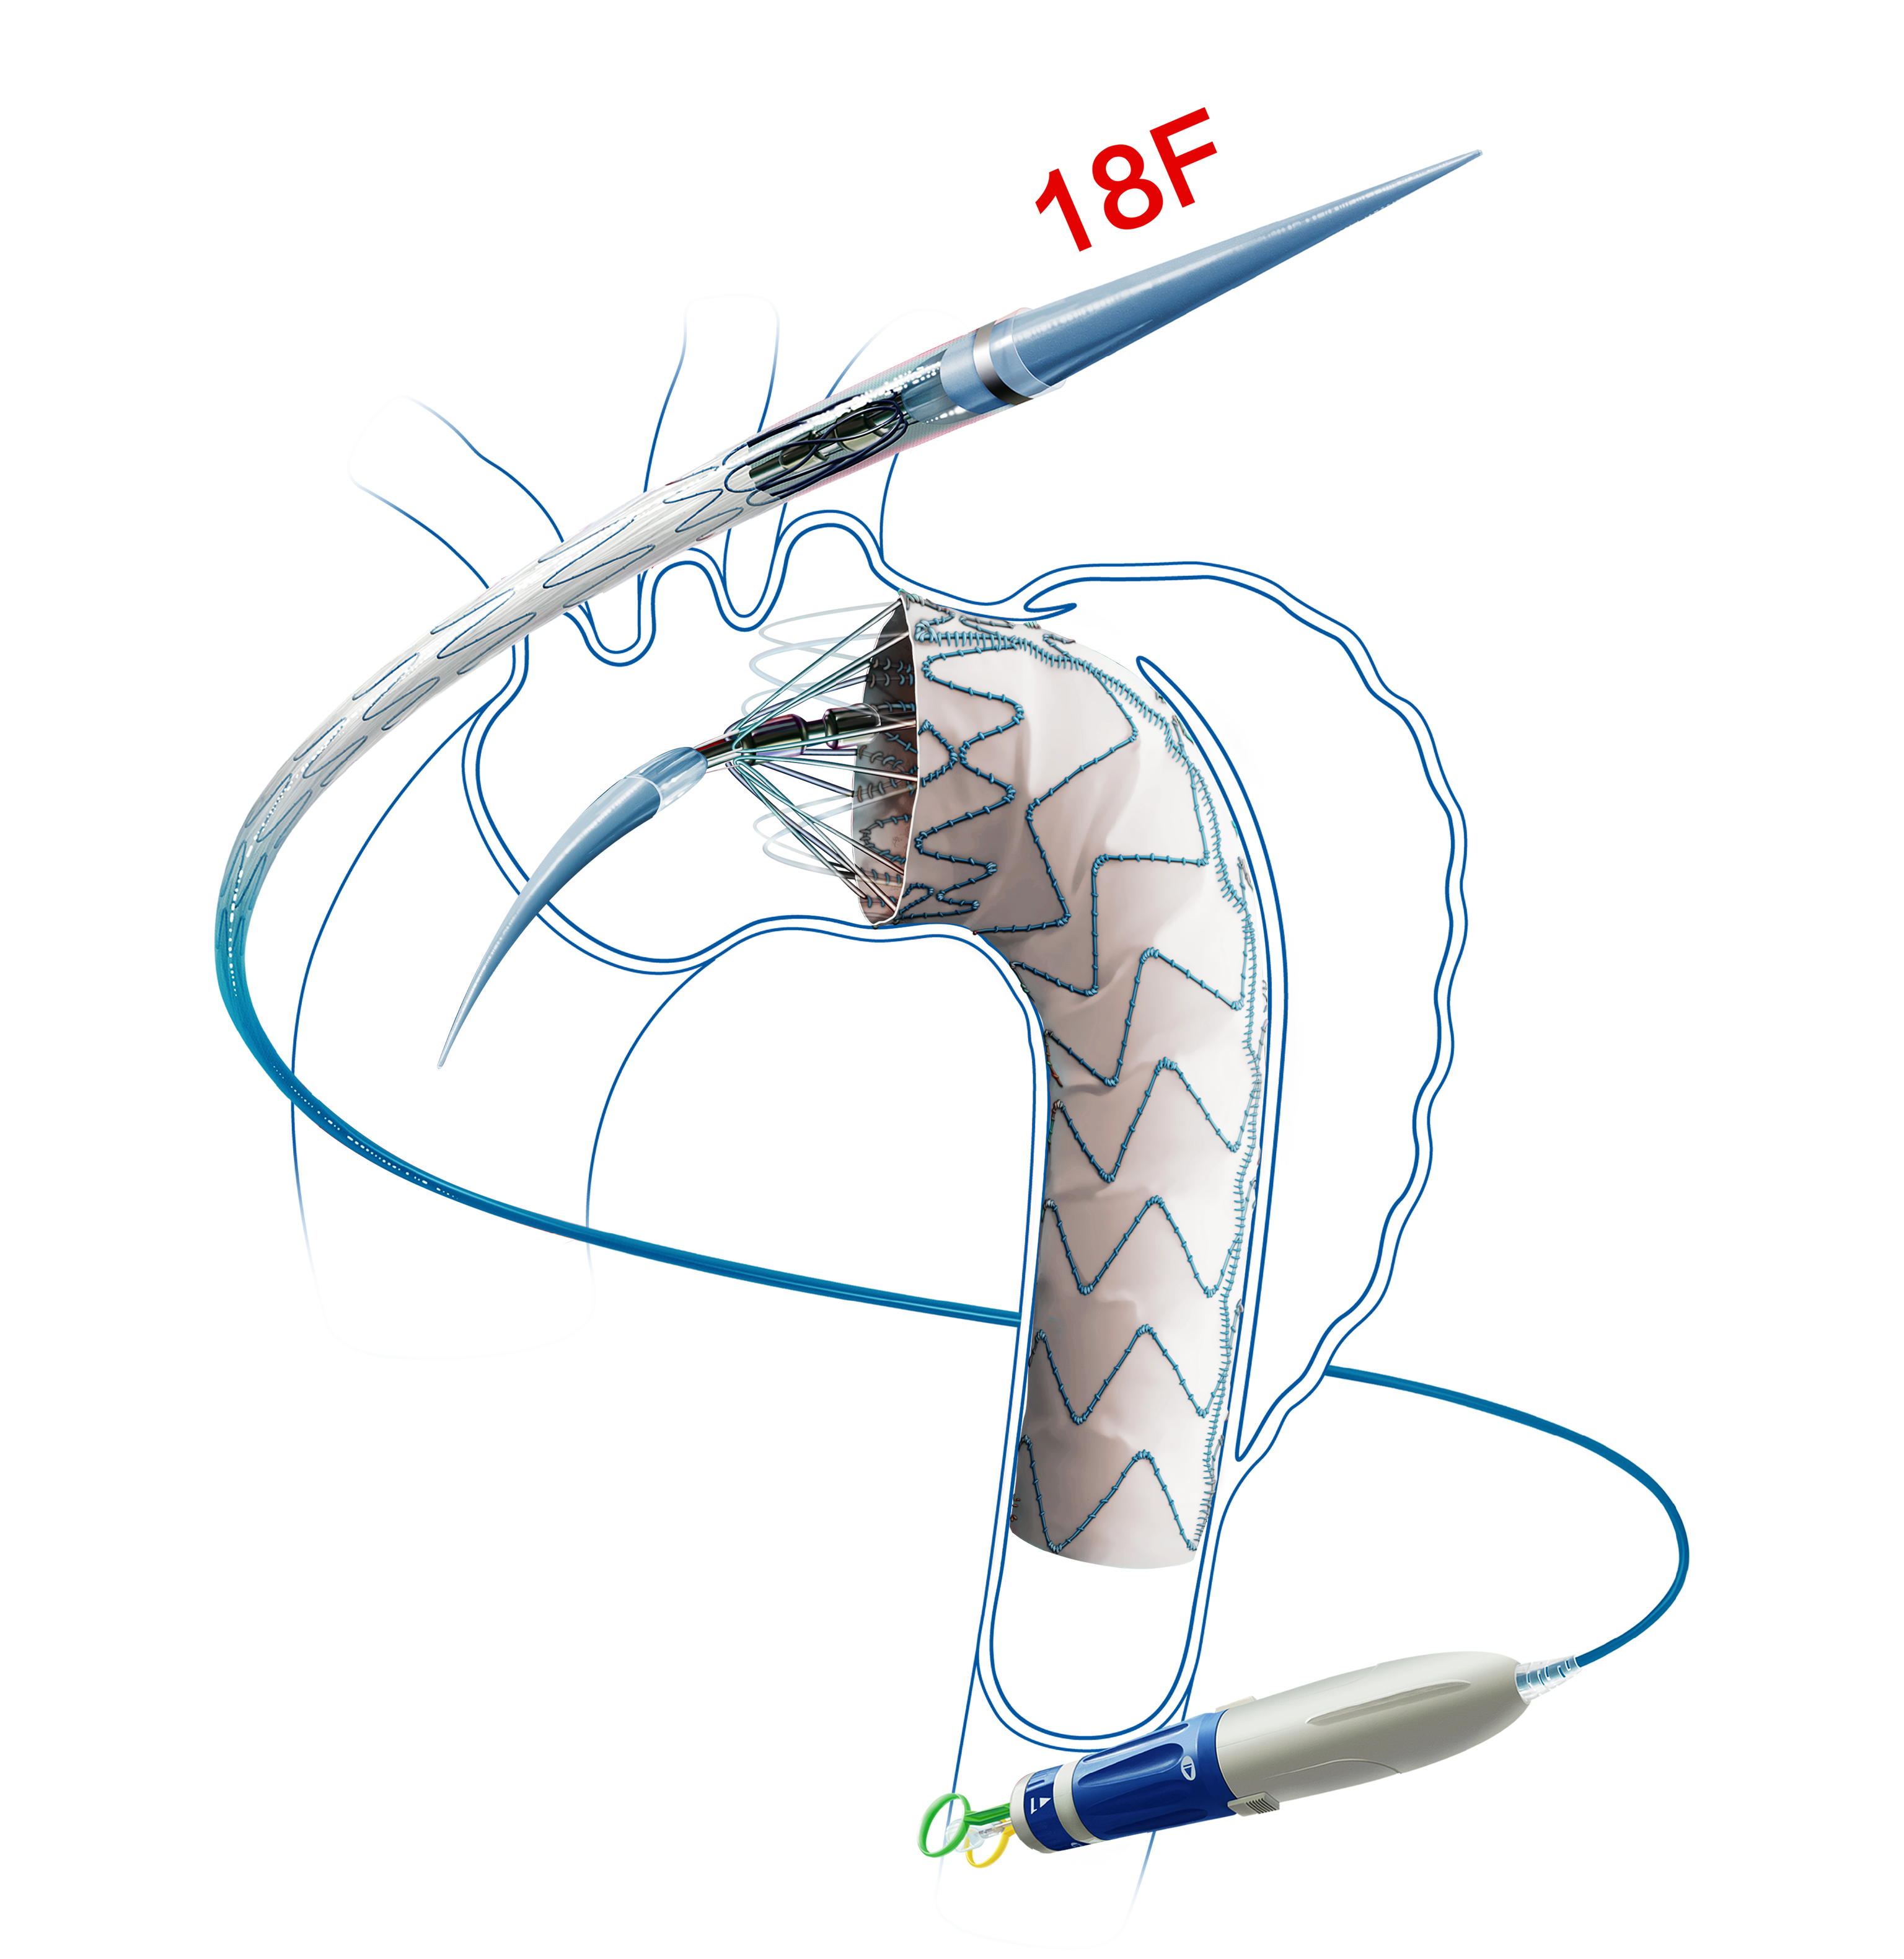

Hercules™ Thoracic Stent Graft System with Low Profile Delivery System is mainly indicated for the treatment of aortic aneurysms confined to straight segments of the blood vessel.